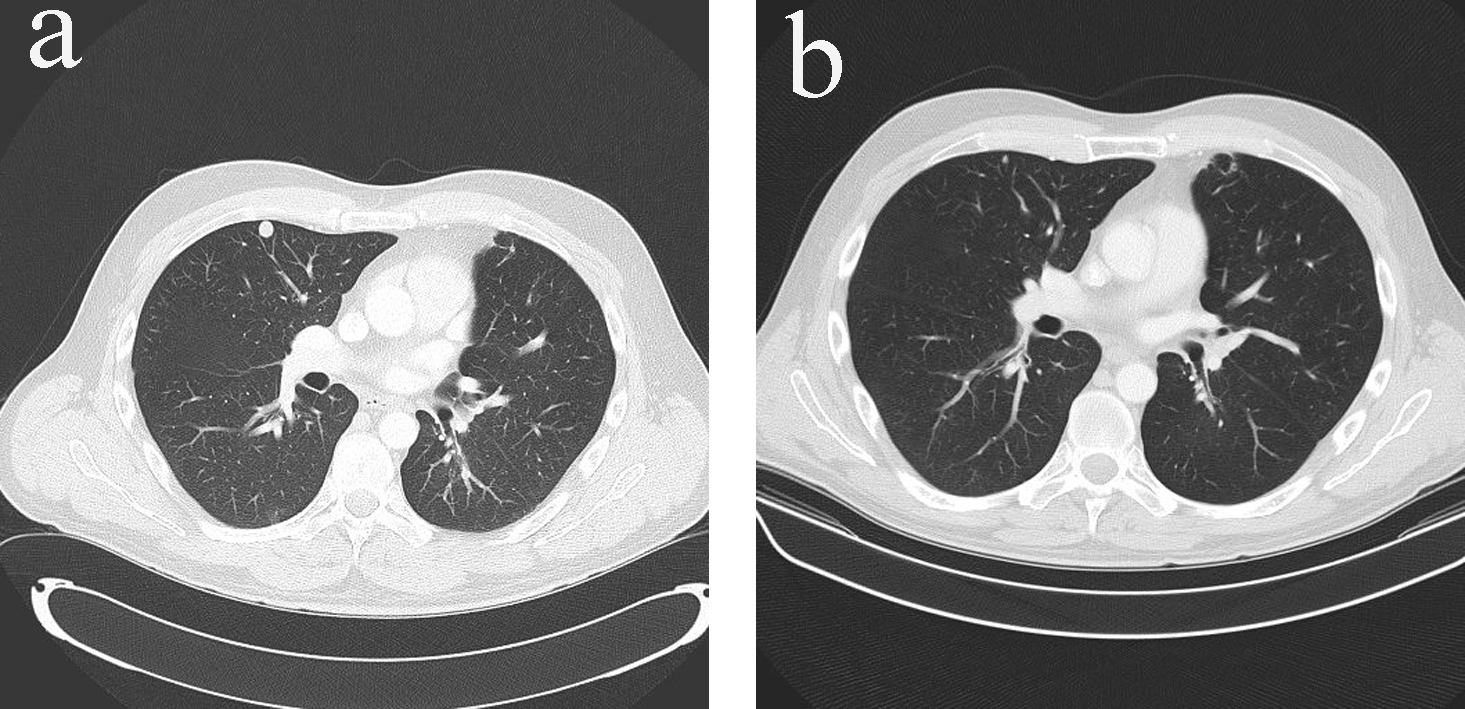

Adjuvant mitotane monotherapy (3 - 6 g/day) together with cortisol replacement was initiated after the surgery. The patient enjoyed disease-free period of 7 months until he developed metastatic disease in bones, lungs and peritoneum (Fig. 4a, 5a). At time of presentation of relapse he was complaining of thoracic back pain which precipitated MRI spine which showed T12 cord compression requiring palliative radiotherapy (30 Gy in 10 fractions). Six cycles of etoposide, doxorubicin and cisplatin (EDP) were added to mitotane over a period of 7 months, resulting in excellent partial response to treatment, i.e. complete response of all peritoneal nodules, near complete response of the multiple pulmonary nodules except one sub-centimeter nodule in each lung and stable bony metastases (Fig. 4b, 5b). The patient is now on mitotane monotherapy only (3 - 6 g/day) with stable disease. Therapeutic enoxaparin was ceased after 27 months of treatment for pulmonary embolism with no further thromboembolic complications.

![]() Click for large image | Figure 4. (a) Pulmonary metastases in CT scan (transverse view) before additional chemotherapy with EDP. (b) Resolution of pulmonary metastases in CT scan (transverse view) after additional chemotherapy with EDP. |